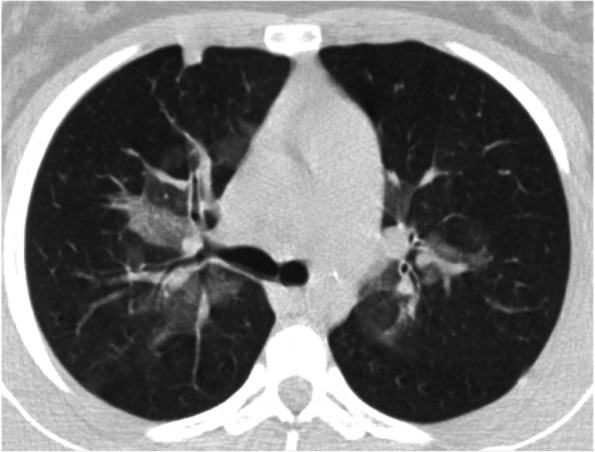

Specifically, EVALI should be suspected in a patient with a history of vaping presenting with respiratory symptoms such as shortness of breath, cough, chest pain, pleuritic chest pain and haemoptysis and/or gastrointestinal symptoms such as nausea, vomiting, diarrhoea and abdominal pain. Systemic symptoms such as fever, tachycardia and tachypnoea may be present. Hypoxemia may be present and progression to respiratory failure is common [ref. 12]. Bloodwork doesn’t show specifical evidences, nevertheless, some elements may be evocative of EVALI: a non-specific raise of the inflammation indexes may be detected. Blood exams may also be useful to exclude other processes in the differential diagnosis [ref. 13, ref. 14]. The radiological evaluation in patients with suspected EVALI generally shows diffuse hazy or consolidative opacities at the chest radiograph. Chest CT would typically show a ground glass imaging with spare of the sub pleural space [ref. 15]. GGOs (Ground-glass opacification) are common, and the most useful imaging features to help differentiate EVALI from COVID-19 are subpleural sparing of pulmonary opacities (GGOs) and centrilobular nodules (infrequent in COVID-19) (Fig. 2). In our case there was no thickening of the interlobular septa, but the reversed halo sign was present (atoll sign) (Fig. 3), which is characterized by the presence of a central ground-glass opacity surrounded by dense consolidation of crescentic shape or complete ring (sign present in late phase COVID-19 and typical of BOOP (bronchiolitis obliterans organizing pneumonia) and Wegener). These findings are consistent with diffuse alveolar damage, as seen in acute respiratory distress syndrome. The radiological findings vary according to the underlying histopathological process. Histology isn’t routinely performed, several pathologic patterns of lung injury have been reported in the setting of vaping such as lipoid pneumonia, diffuse alveolar damage, acute eosinophilic pneumonia, organizing pneumonia, diffuse alveolar haemorrhage, respiratory bronchiolitis interstitial lung disease, hypersensitivity pneumonitis and giant cell interstitial pneumonia, prompting the heterogeneity of the underlying disease processes. [ref. 16–ref. 21]. At the broncho alveolar lavage fluid (BAL) of affected patients the most commonly found substances appeared to be tetrahydrocannabinol (THC) and/or vitamin E acetate, the presence of lipid-laden macrophages seen with oil red O staining has been reported as well [ref. 22, ref. 23]. Vitamin E had been recently looked at as possible culprit in the pathogenesis of EVALI as multiple studies report its presence in the BAL samples from patients affected from EVALI, while it hasn’t been detected in healthy individuals [ref. 9, ref. 23]. Vitamin E is often used as a thickening agent of illegal THC containing vapes. According to the American public health authorities, in order to formalise the diagnosis of EVALI, vaping should be present within 90 days prior to the symptom onset, an underlying infectious cause needs to be ruled out and there should be no evidence of other plausible diagnoses (e.g. cardiac, rheumatologic or neoplastic processes) [ref. 9, ref. 24].